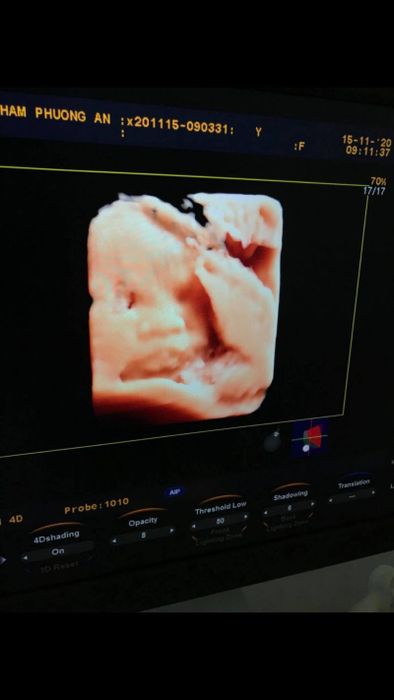

4. Phuong An Clinic

For another reliable option for prenatal ultrasound in Can Tho, you can consider Phuong An Clinic. This clinic is trusted and highly rated for its enthusiasm and accurate conclusions. Here, modern equipment and facilities with high-quality standards, along with highly qualified and responsible doctors, prioritize your well-being. At Phuong An Clinic, expect the most accurate ultrasound and prenatal care. Additionally, the clinic offers various medical services, gynecological examinations, color ultrasound, urine tests, and more.